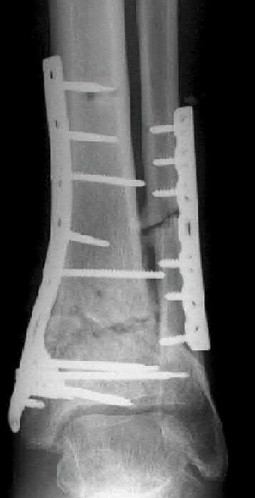

Figure A demonstrates an AP radiograph of a Weber B fibula fracture with minimal medial clear space widening.

Figure B demonstrates a mortise radiograph of a Weber B fibula fracture with a congruent mortise.

Figure C demonstrates a lateral radiograph of a Weber B fibula fracture with a congruent mortise.

Figure D demonstrates a stress radiograph with minimal medial clear space widening.

Figures A to C show radiographs of a 70 year-old male who fell on the ice 5 days ago. He could initially walk after the fall, but he is now unable to weight-bear on the leg due to pain. Physical examination shows diffuse ankle swelling, with no medial sided ankle tenderness. He is neurovascularly intact. The patient does not smoke and has no medical history. A gravity stress radiograph is demonstrated in Figure

D. After closed reduction, there is 2 mm of fracture displacement, no talar shift and the talocrural angle = 83 degrees. What is the most appropriate treatment?